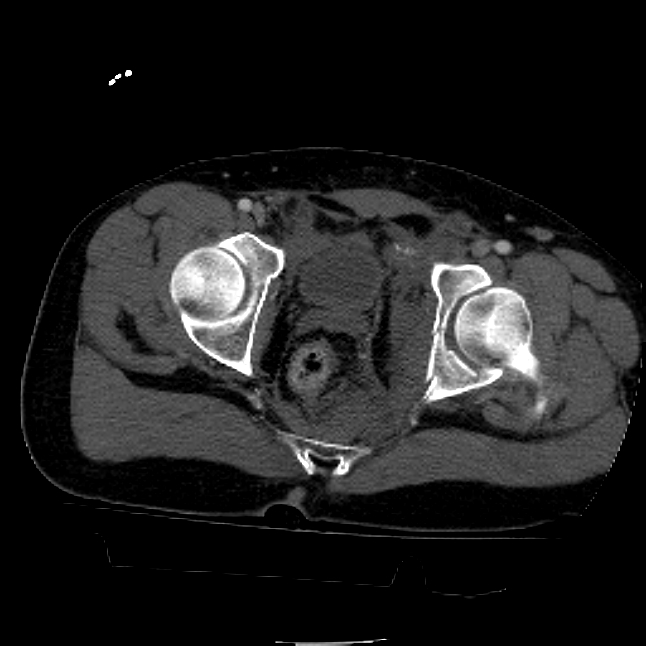

25 yo brittle diabetic, became hypoglycemic and passed out on his motorcycle. Sustained bilateral lateral Hoffa fractures with associated LCL injury on the right and right distal radius fracture. I have questions regarding his pelvic ring/acetabular fracture on the left. Appears to be a very low posterior column fracture with associated posterior wall, marginal impaction. Superior and inferior rami fractures as well on the left giving him a floating segment of inf ramus/ischium/posterior column, but no detectable posterior ring injury. Should the posterior column/posterior wall fracture be addressed surgically because of the marginal impaction? Or is this fracture low enough to be treated non-operatively? I appreciate the input.

It's an interesting case. The plain films show the impaction, but most of the joint looks pretty good. The CT cuts look awful, though.

The impaction is so big I don't think I would ignore it. It IS down low, but it takes up almost the whole southern hemisphere of his joint.